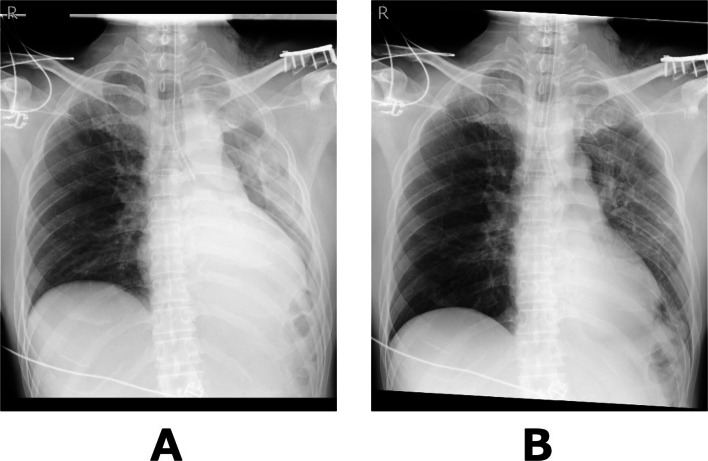

Postoperatively, chest radiography performed while OLV was still in place showed decreased inflation of the left lung (Fig. 3A). Gentle manual ventilation was performed for approximately 1 min at airway pressures of 10–15 cmH₂O, and a follow-up chest radiograph confirmed re-expansion of the left lung (Fig. 3B). The patient was then awakened and extubated. On postoperative day 1, chest radiography showed further improvement in left lung inflation and no evidence of pneumothorax (Fig. 4). The patient had no postoperative complications and was discharged home on postoperative day 2. The patient remained well during outpatient follow-up, with no evidence of pneumothorax recurrence or respiratory symptoms.

Fig. 4.

Chest radiography on postoperative day 1 showing further improvement of left lung inflation